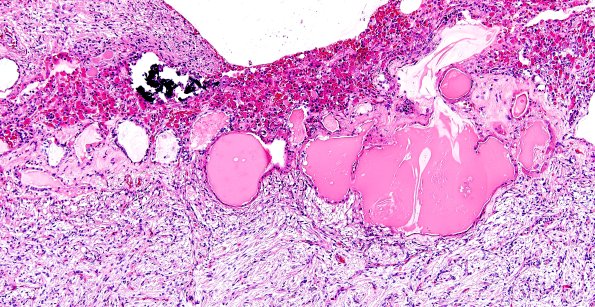

7A1-3 The intermediate lobe consists of many small epithelium lined cysts in this case which are thought to represent the residua of Rathke’s pouch. (H&E)